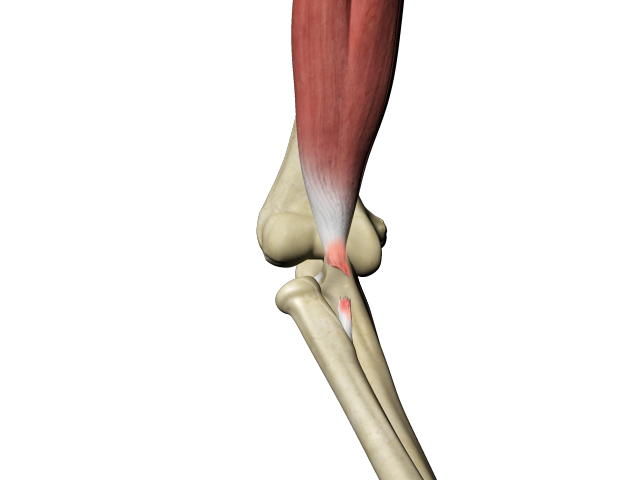

Biceps Tendon Repair

Biceps tendon repair is a surgical procedure to restore a biceps tendon that has been torn or ruptured by severe trauma or injury.

Distal Biceps Repair

The biceps is a large muscle located in the front of your upper arm and runs from the shoulder to the elbow joint.